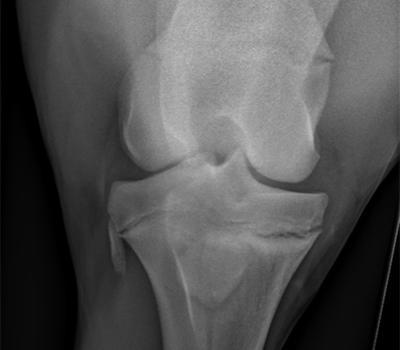

Radiology

Bay Equine use the latest digital x-ray machines to produce the highest quality images. Images are able to be viewed at the horse’s side to allow an immediate treatment plan to be instituted. The digital images are stored on a server, so they are accessible anywhere, any time. This makes it possible to email radiographs to other veterinarians around the world or directly to clients upon request.

Digital radiographs are often required for detailed prepurchase examinations to assess your purchase for conditions such as osteoarthritis, osteochondral (chips) bone fragments, osteochondritis dissecans (OCD’s) and bone cysts.